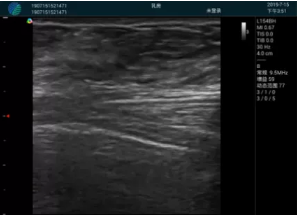

頸動脈血流充盈飽滿,無外溢

肝內(nèi)血管顯示清晰,血流敏感無外溢

甲狀腺囊性結(jié)節(jié),囊壁鈣化,透聲好

甲狀腺囊性占位